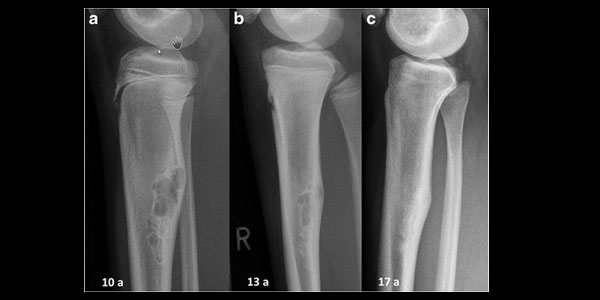

Ewing Sarkom

Kemiğin küçük yuvarlak hücreli kötü huylu tümörü. Yıllık insidansı 3-4:1 milyondur. Sıklıkla genç hastalarda (<20 yaş) ortaya çıkar. En sık uzun kemiklerin (femur, humerus vs) diafizinde, pelviste ve skapula da saptanır.